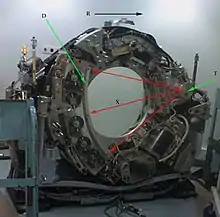

D: detectores de radiación.

T: tubo emisor de rayos X.

X: haz de rayos X.

R: rotación del "gantry".

El aparato de TC emite un haz colimado de rayos X que incide sobre el objeto que se estudia. La radiación que no ha sido absorbida por el objeto es recogida por los detectores. Luego el emisor del haz, que tenía una orientación determinada (por ejemplo, estrictamente vertical a 90º) cambia su orientación (por ejemplo, haz oblicuo a 95º). Este espectro también es recogido por los detectores. El ordenador 'suma' las imágenes, promediándolas. Nuevamente, el emisor cambia su orientación (según el ejemplo, unos 100º de inclinación). Los detectores recogen este nuevo espectro, lo 'suman' a los anteriores y 'promedian' los datos. Esto se repite hasta que el tubo de rayos y los detectores han dado una vuelta completa, momento en el que se dispone de una imagen tomográfica definitiva y fiable.